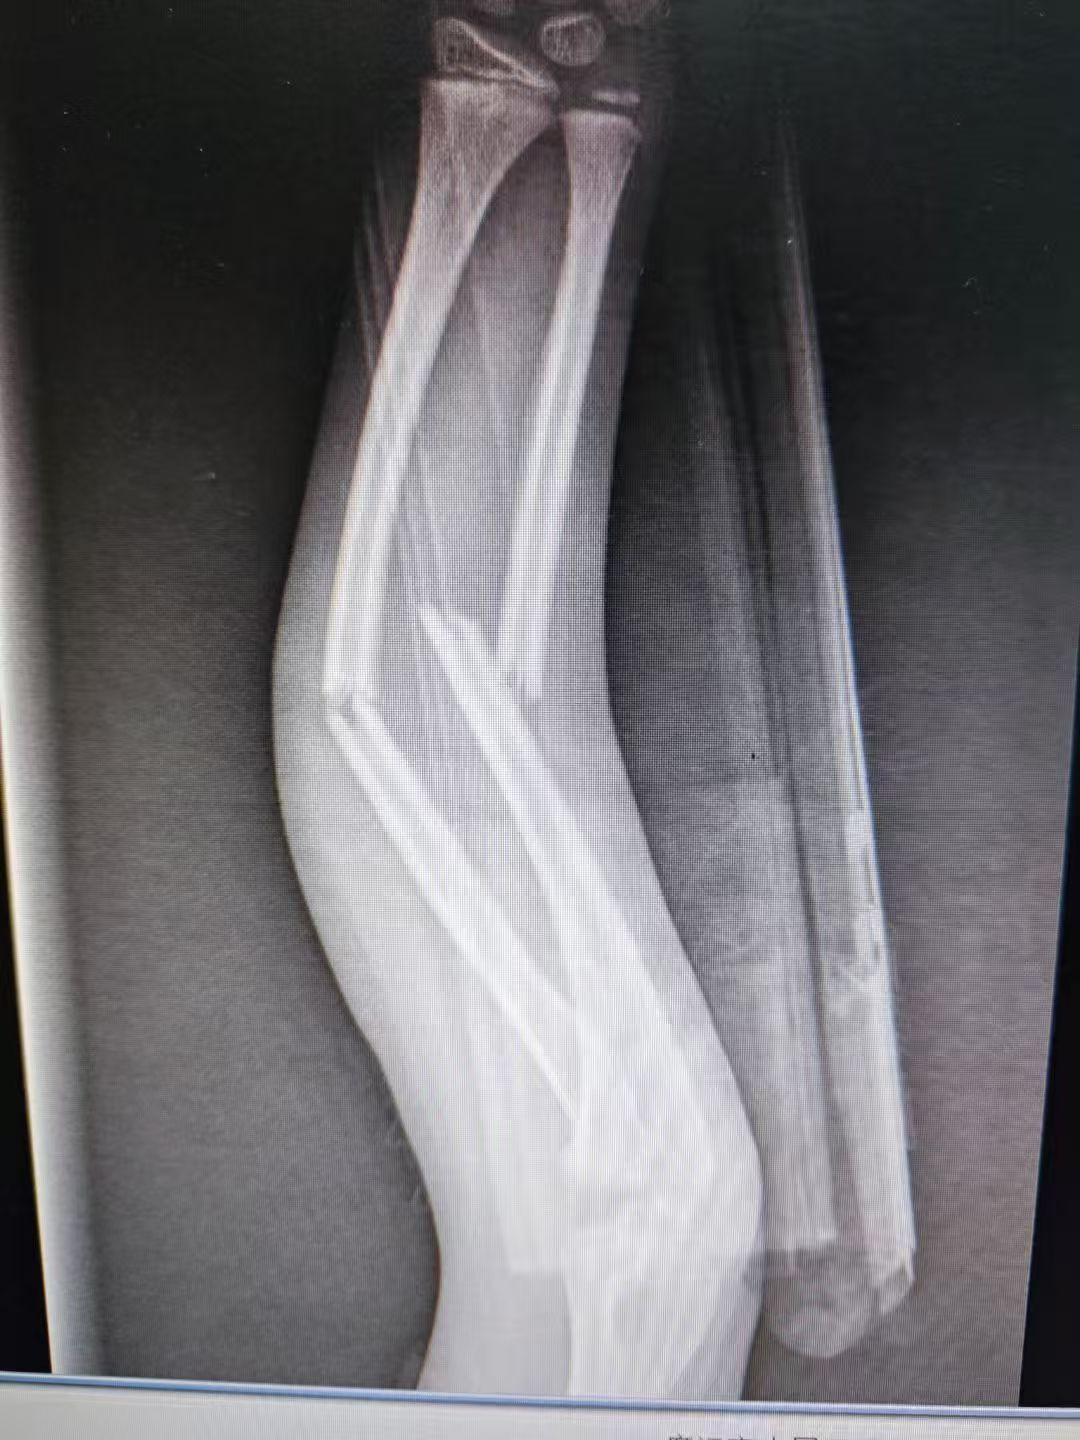

图片图片图片

儿童尺桡骨双骨折闭合复位微创弹性髓内针内固定